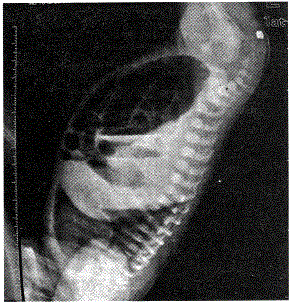

问题 如图所示X片可考虑诊断为

选项 A.先天性巨结肠 B.高位肛门闭锁 C.中位肛门闭锁 D.低位肛门闭锁 E.消化道穿孔

答案 B